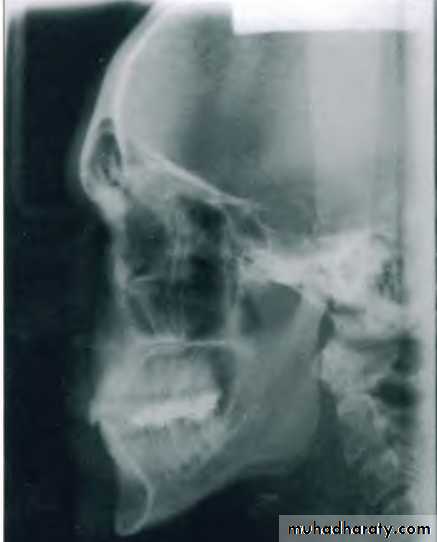

Types of cephalogramsLateral cephalometric

Taken with head in a standardized reproducible position at a specific distance from X-ray source

Uses :

Important in orthodontic growth analysisDiagnosis & Treatment planning

Monitoring of therapy

Evaluation of final treatment outcome